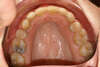

Vues après le traitement